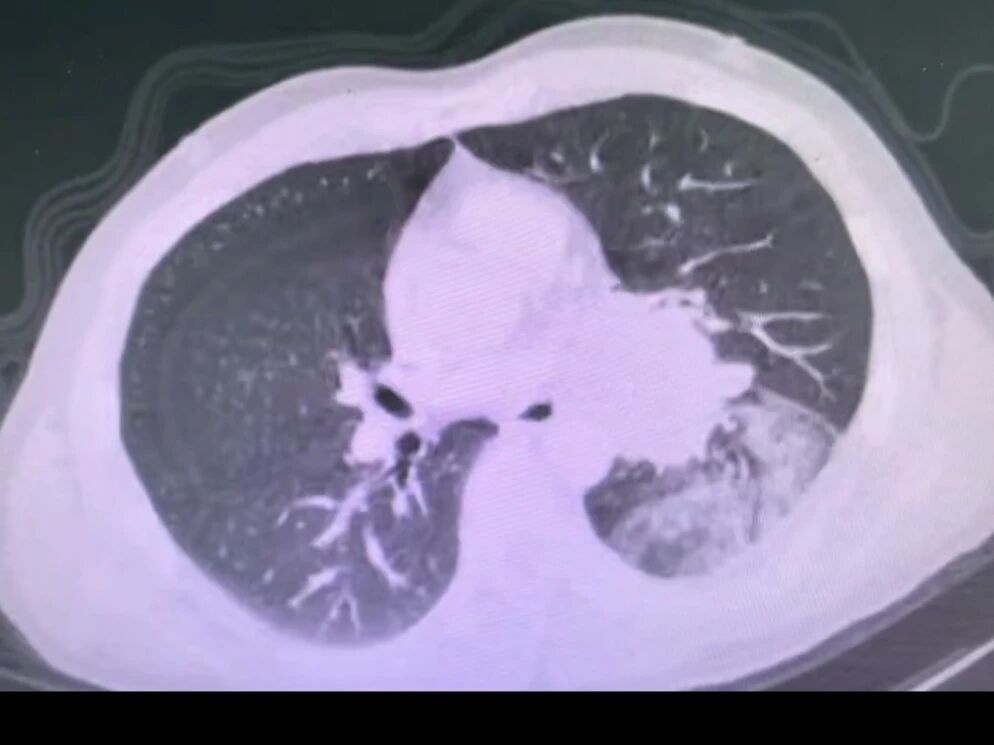

1775811334299774.jpg

胸部ct提示左肺门巨大占位,包绕肺门主要结构